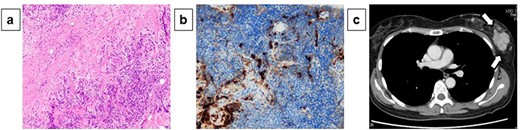

A 54-year-old woman presented with a tumor in her left breast. The patient had no relevant medical or family history. During physical examination, an elastic hard mass measuring ~6 cm in size was palpated in the upper-outer area of the left breast (Fig. 1a). An induration of ~4 cm was also found on the right cheek (Fig. 1b). Mammary ultrasonography revealed an irregular hypoechoic tumor of measuring 45.0 × 43.0 × 32.0 mm in size in the upper-outer quadrant of the left breast (Fig. 1c). Core-needle biopsy performed in the same site revealed a high degree of mixed T and B lymphocytic and plasma cell infiltration, as well as interstitial fibrosis (Fig. 2a). Many plasma cells were IgG positive, of which >40% were IgG4 positive (Fig. 2b). These biopsy findings led to a diagnosis of IgG4-RM of the left breast. Computed tomography exhibited no significant findings besides the left mammary mass and left axillary swelling (Fig. 2c). IgG4-RD was diagnosed based on hematological examination results revealing elevated serum IgG4 levels (332 mg/dl). Based on comprehensive diagnostic criteria for IgG4-RDs, we diagnosed the patient with IgG4-RM. The condition was treated with prednisolone (30 mg/day, 0.6 mg/kg/day) for 4 weeks, which resulted in a decrease in the tumor size. The patient is currently being followed up with maintenance therapy.

Pathological diagnosis of core-needle biopsy specimens and computed tomography findings: Core-needle biopsy performed in the same site revealed a high degree of mixed T and B lymphocytic and plasma cell infiltration, as well as interstitial fibrosis (×200) (a). Many plasma cells were IgG positive, of which >40% were IgG4 positive (×200) (b). Computed tomography exhibited no significant findings besides the left mammary mass and left axillary swelling (c).